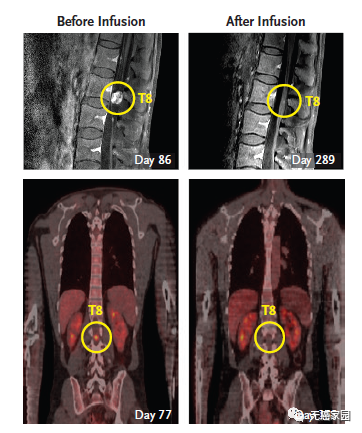

脑室内注射CAR-T细胞,首次消灭实体瘤

2016年12月,NEJM曾报道过1例利用CAR-T技术治疗脑胶质瘤的案例。一名50岁的男性,确诊为高级别脑胶质瘤,先后做了手术、放疗、替莫唑胺化疗等常规治疗,6个月后疾病复发。这时他参加了一项临床试验,接受靶向IL13Rα2的CAR-T治疗。不过这个疗法,有些“惊悚”。

主管医生通过核磁共振检查发现:这位病友脑部有5个病灶;因此,先通过手术切掉其中的三个大的,还剩下两个较小的由于位置深,无法切除。主管医生就给他的病灶处直接插了一个管子,然后通过这个管子,把CAR-T细胞打了进去,分3个批次,进行了多次的细胞回输。最终,肿瘤完全消失,疗效维持了8个月左右。

第二轮CAR-T疗法结束后,Richard Grady脊索内肿瘤出现剧烈萎缩

目前,CAR-T疗法治疗脑瘤的前瞻研究国内也在积极的开展临床试验,大家可致电无癌家园医学部了解详情。